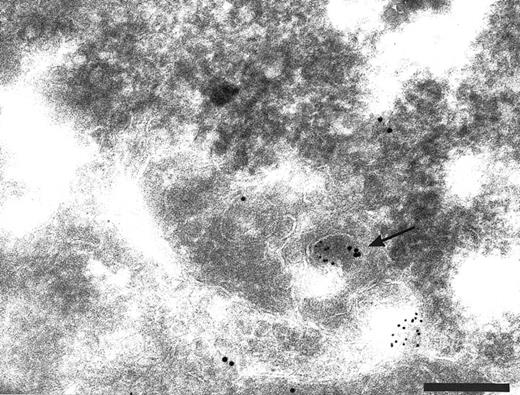

To investigate whether endogenous membrane-bound TFPI in HUVEC was being internalized, newly internalized surface biotin was colocalized with TFPI using antibodies on cryosections through biotinylated cells that had been incubated for 30 minutes at 37°C. Biotin-specific antibodies bound to sites within labeled cells that also contained anti-TFPI label. These structures included small vesicles close to the cell surface (Fig 6A) and in larger vesicles (Fig 6B) similar to those that accumulated DAMP and labeled with anti-LAMP 1 antibodies. Although it is possible that the internalized biotin is being transported to endocytic structures involved in TFPI storage, it is more likely that the TFPI is being co-internalized with the surface biotin.

Cryosections of HUVEC incubated with biotin before endocytosis and fixation. The cell surface labeled with anti-TFPI (large gold) and anti-biotin (small gold). Colocalization of anti-TFPI and anti-biotin was seen in small vesicles close to the cell surface (A, arrow) and in larger vesicles (panel B). Bars = 0.2 μm.